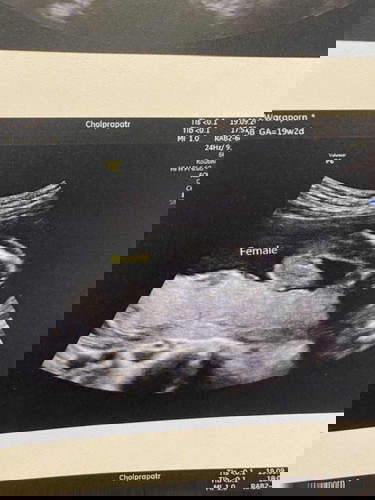

คุณหมอบอกว่า ผู้หญิง น้องผู้หญิงจริงๆใช่ไหมคะ5555

เห็นหลายๆคนคลอดออกมาเป็นผู้ชาย แต่ซาวด์ออกมาเป็นแบบนี้ ชัดใช่ไหมคะว่าผู้หญิง

ผู้หญิงแน่นอนจ้า